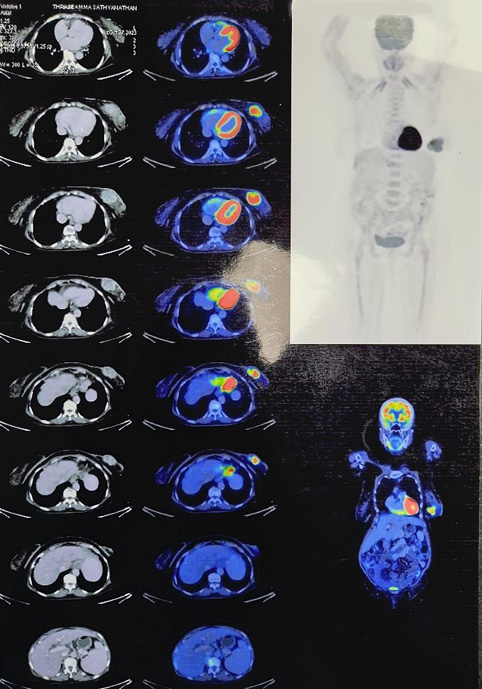

An 80-year-old female k/c/o HTN, COPD, hypothyroidism, and JAK 2 mutation positive polycythaemia vera presented with lump left breast of 8 months duration. No history suggestive of locoregional or distant metastases. On examination 6x4 cm lump retro areolar region, irregular surface, hard in consistency, fixed to breast tissue and overlying skin, not fixed to the chest wall. No palpable axillary lymphadenopathy, exa­mination of right breast was normal. Sono mammogram showed Lobulated hypoechoic lesion measuring 4.4x3.2x4.7 cm from 5 to 7 o’clock region in retro and periareolar region – BIRADS-V. Two clustered areas of pleomorphic calcifications in upper outer and central quadrants – BIRADS-4b (Figure 1). F18 FDG PET CT scan showed large heterogeneously enhancing FDG avid soft tissue mass with spiculated margins measuring 46x42x43 mm (max SUV – 13.2) in retro areolar region extending to lower quadrant. The lesion is seen abutting the overlying skin, the planes with underlying muscles maintained. No abnormal enhancing or FDG avid lesion in brain, lungs, liver, adrenal or skeleton (Figure 2). USG guided Core needle biopsy was done which revealed metaplastic carcinoma of adenosquamous type. ER, PR-positive, HER 2 Neu-Negative.

Figure 2. PET CT images showing large heterogeneously enhancing FDG avid soft tissue mass with spiculated margins measuring 46x42x43 mm (max SUV – 13.2)